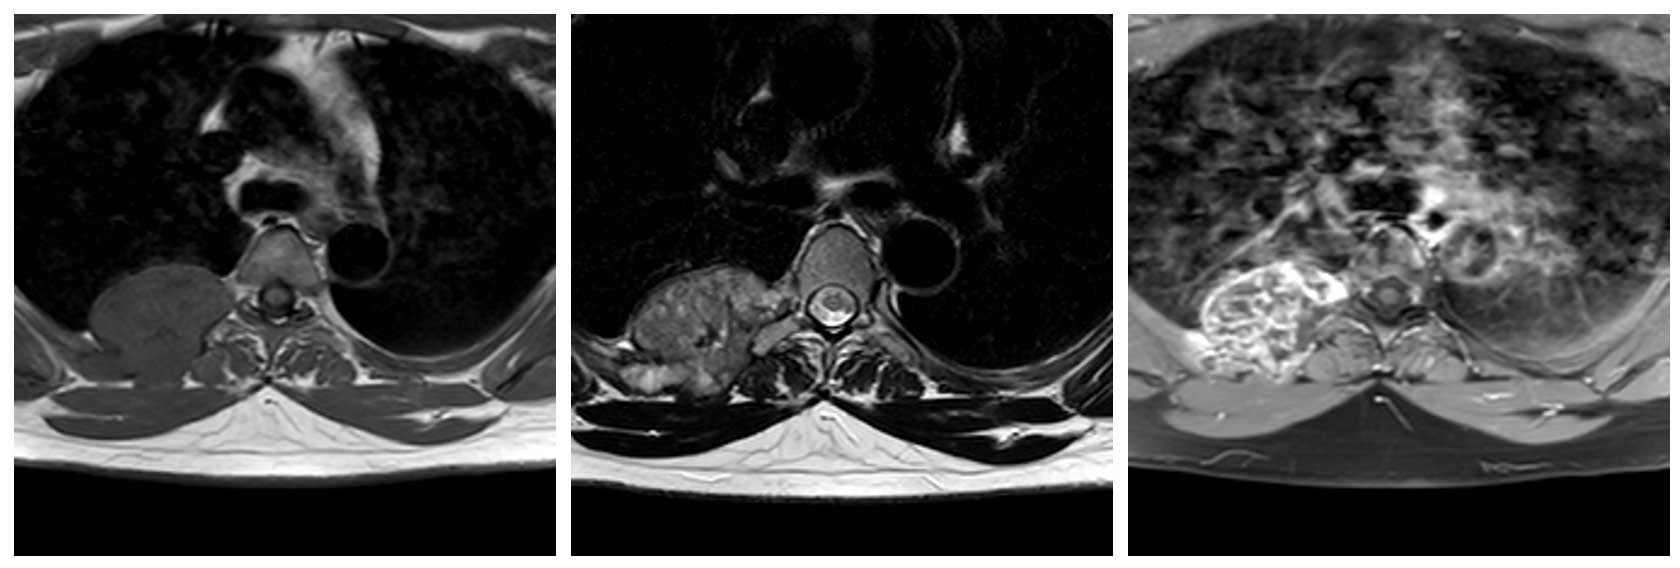

Ameliyat Öncesi: MR’da göğüs kafesi sağ taraf yerleşimli kaburgada yıkıma neden olan heterojen kıkırdak içerikli tümör görülmekte.